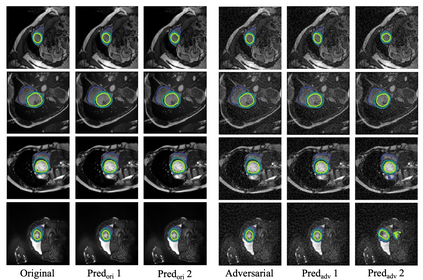

In this paper, we aim to improve the performance of semantic image segmentation in a semi-supervised setting in which training is effectuated with a reduced set of annotated images and additional non-annotated images. We present a method based on an ensemble of deep segmentation models. Each model is trained on a subset of the annotated data, and uses the non-annotated images to exchange information with the other models, similar to co-training. Even if each model learns on the same non-annotated images, diversity is preserved with the use of adversarial samples. Our results show that this ability to simultaneously train models, which exchange knowledge while preserving diversity, leads to state-of-the-art results on two challenging medical image datasets.